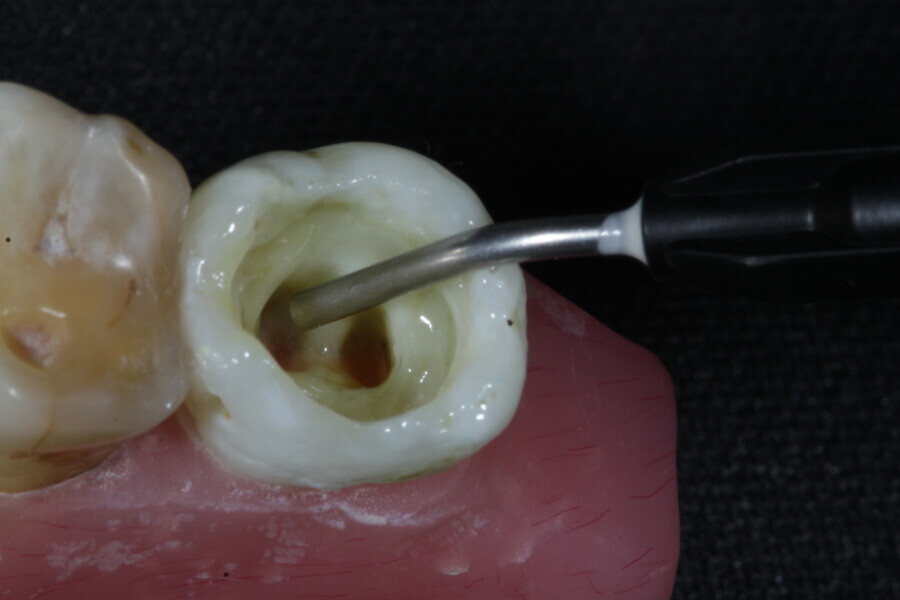

The second step focuses on reinforcing the restoration through careful fibre and FRC selection and placement. Tooth preparation should involve minimal removal of tooth structure to preserve as much natural tooth as possible in preparing the cavity for the restoration. Fibres or layers of FRC (flowable, paste, cube, etc.) are then strategically placed within the prepared tooth and composite material to reinforce areas susceptible to high stress and occlusal forces based on occlusal contact mapping. This strategic selection and placement of fibres and layers of FRC is crucial for enhancing the strength and longevity of the restoration.

The third step is to restore the tooth to its natural form, function and aesthetics. Composite resin, along with fibres or fibre-reinforced flowable or fibre-reinforced dentine substitute materials, is carefully applied to the prepared tooth structure. A layering technique is often used to ensure proper adhesion and integration of the reinforced materials with the composite material, enhancing the overall strength and functionality of the restoration. The composite resin is then polymerised using a curing light, ensuring that the materials are securely bonded within the restoration and providing a stable and long-lasting result. During this restorative process, the clinician should take special care not to expose fibres or FRC layers to the oral environment, as this can cause tissue irritation and water absorption by the materials in the long run. Therefore, the final layers of the restoration should always be a suitable aesthetic conventional composite resin.

1. direct restoration using a fibre-reinforced flowable composite and membrane cube after endodontic treatment (Figs. 21–35); and